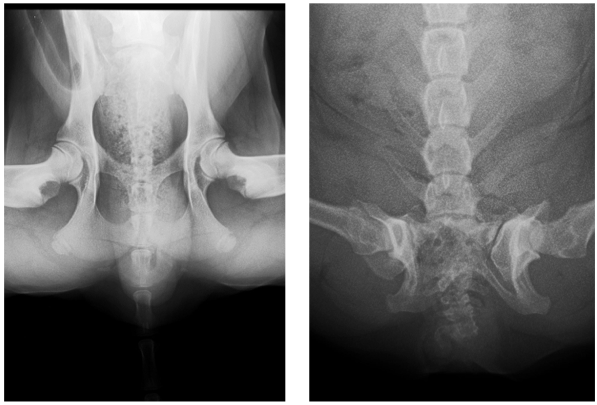

Dysplazje stawów biodrowych

Dysplazje stawów biodrowych polegają na nieprawidłowym dopasowaniu głowy kości udowej do panewki stawu biodrowego. Prowadzi to do niestabilności stawu oraz stopniowego uszkadzania chrząstki stawowej, a co za tym idzie, powstawania zwyrodnień i powstawania biodra płaskiego (coxa plana).

Diagnostyka dysplazji

Rozpoznanie dysplazji opiera się na badaniu ortopedycznym oraz diagnostyce obrazowej. Najczęściej stosowane badania to:

- badanie kliniczne i ortopedyczne,

- badanie rentgenowskie (RTG),

- tomografia komputerowa (TK),

- artroskopia diagnostyczna.

Badania te pozwalają ocenić stopień zmian oraz zaplanować odpowiednie leczenie.